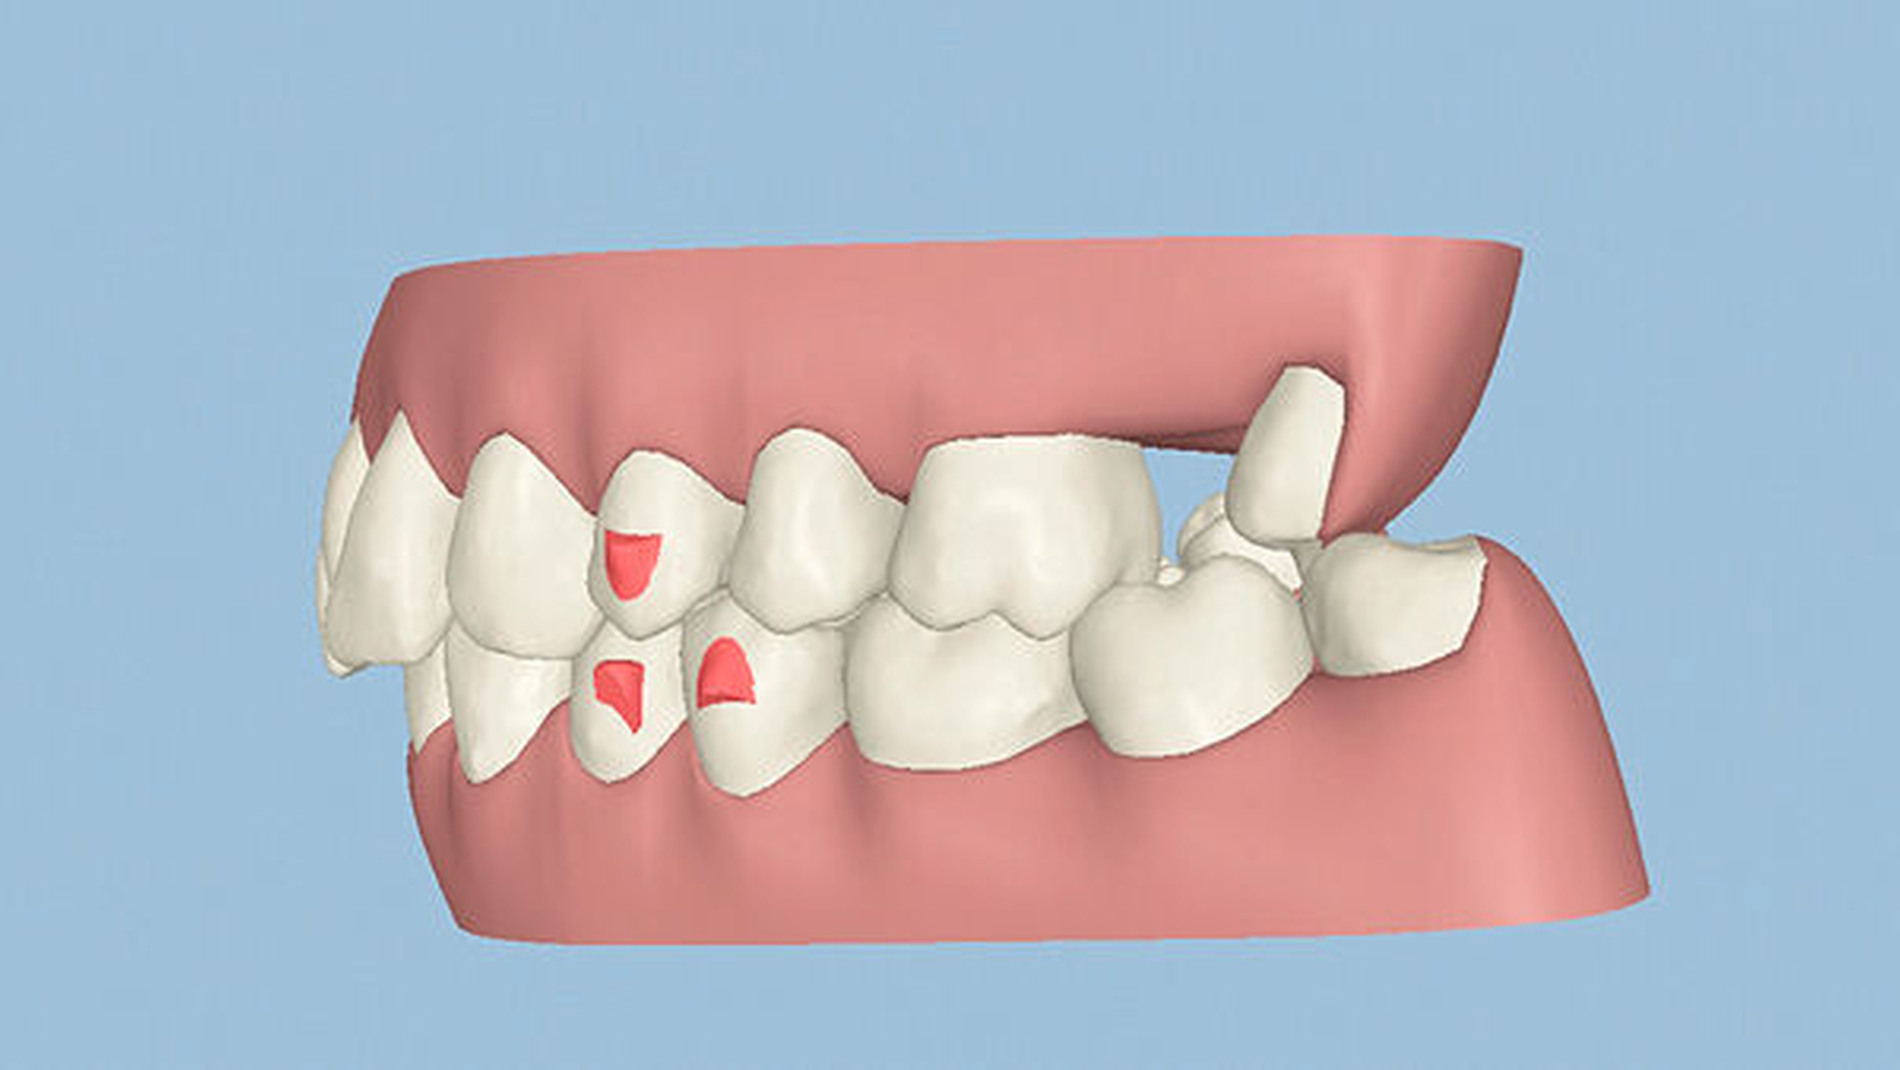

Die Sulkustiefen konnten auf etwas weniger als 4 mm reduziert werden, während der Blutungs- und Plaque-Index bei weniger als 15 Prozent lag. Daher wurde eine kieferorthopädische Behandlung über die nächsten zwei Jahre in Kombination mit engen zahnärztlichen Kontrollen geplant. Als Mittel der Wahl entschieden wir uns gemeinsam mit dem Patienten für das Invisalign-System, da hiermit sowohl eine Schienung als auch eine kraft-arme Bewegung der Zähne möglich sein sollte. Für den Frontzahnbereich wurden keine Attachments geplant, so dass hier eine unnötige Hebelwirkung umgangen werden konnte (Abbildung 3).